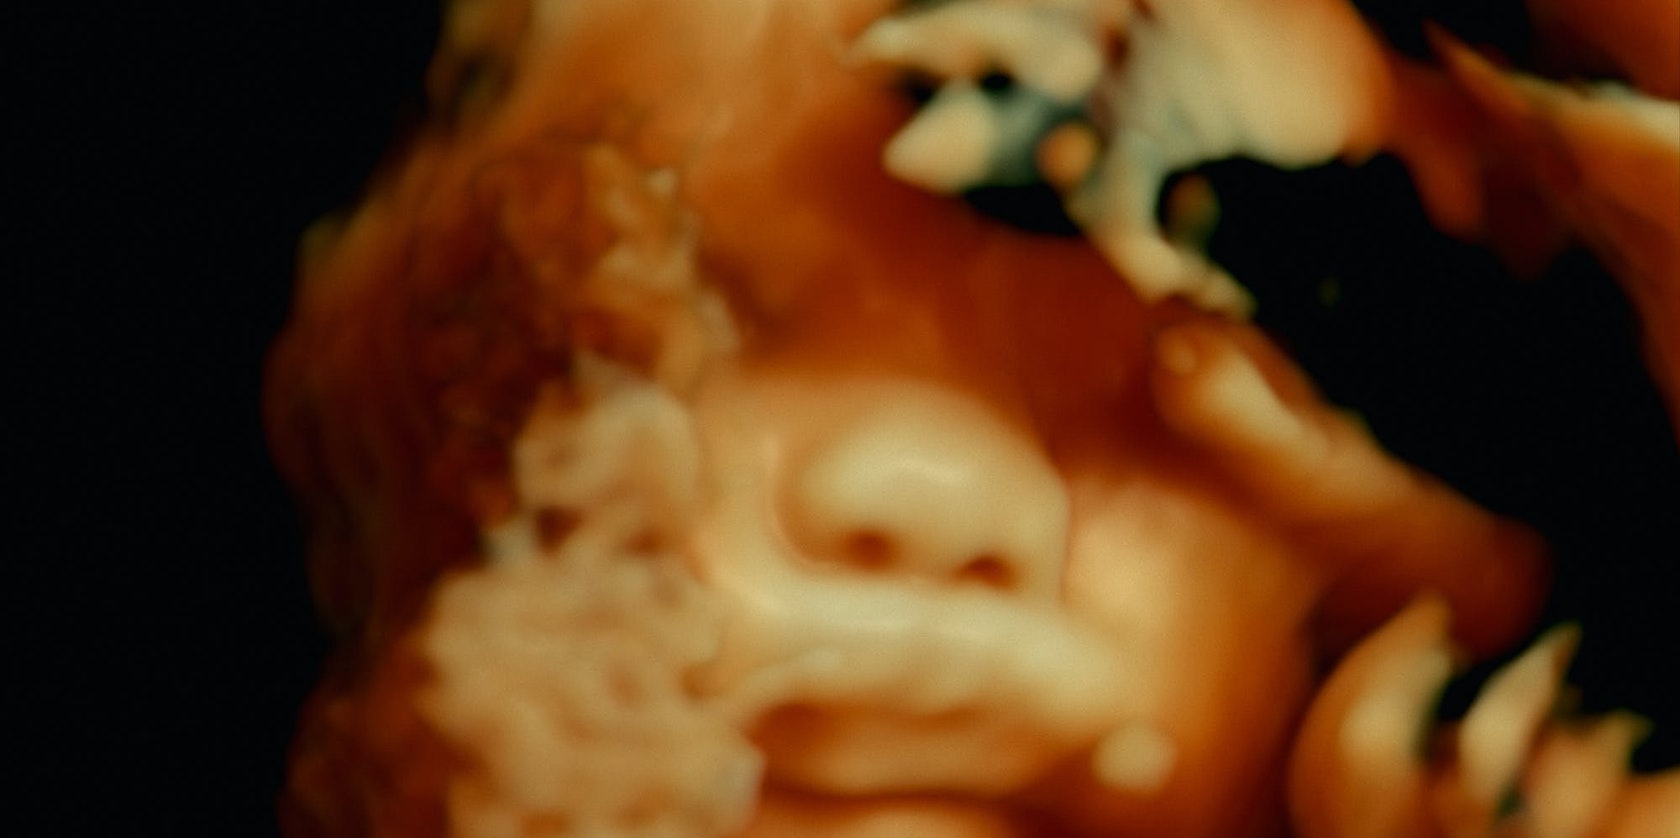

Antropoloog-filmmakers Véréna Paravel en Lucien Castaing-Taylor nemen de mens en de medische wereld onder het mes in hun hoogtechnologische update van de anatomiestudie De Humani Corporis Fabrica. Visueel vergaand weefsel tussen documentaire en sciencefiction.

De humani corporis fabrica, vernoemd naar Vesalius’ baanbrekende anatomiestudie, neemt je doorheen het menselijk lichaam zoals nooit tevoren. Met chirurgische precisie versnijdt het antropologen- en filmmakersduo Véréna Paravel en Lucien Castaing-Taylor 350 uur beeldmateriaal uit 30 gespecialiseerde ziekenhuisdiensten in Parijs. Wanneer een camera niet groter dan een kogel door de innerlijke ruimte van de mens schiet, oogt het eigen lichaam vijandig als een vreemde planeet, terwijl aan de operatietafel alledaagse gesprekken weerklinken. Confronterend en duizelingwekkend als in hun vissersdocu Leviathan (2012) en kannibalengetuigenis Caniba (2017), blijven de documentairemakers dicht op de huid van de artsen en gaan ze ver onder die van de patiënten. Alles wat je niet krijgt te zien en horen in een doordeweekse ziekenhuisserie. Cinema als keizersnede, niet voor gevoelige kijkers.